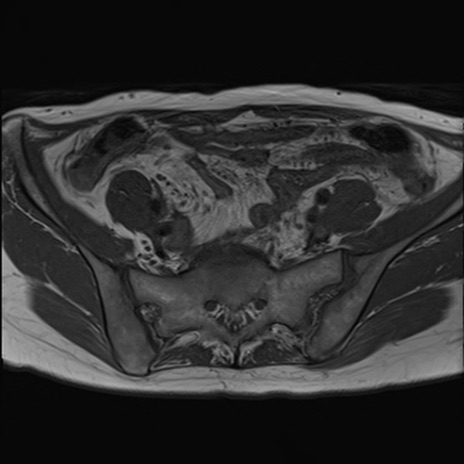

症例39 T1WI(横断像)

MRI(4日後)